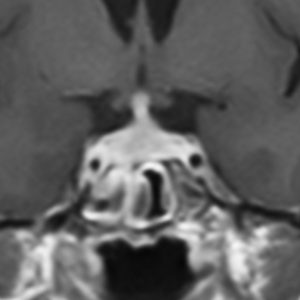

MRI

- 治療の前に必ずガドリニウム造影剤を使って全部の脳と脊髄を検査します

10歳くらいから身長の伸びが遅くなって,12歳で食欲低下と体重減少がありました。左のMRIはガドリニウム造影MRIで,視床下部と下垂体を侵す神経下垂体ジャーミノーマです。CTでは小さな石灰化(白い点)がみえます。CT検査は不必要なものでした。